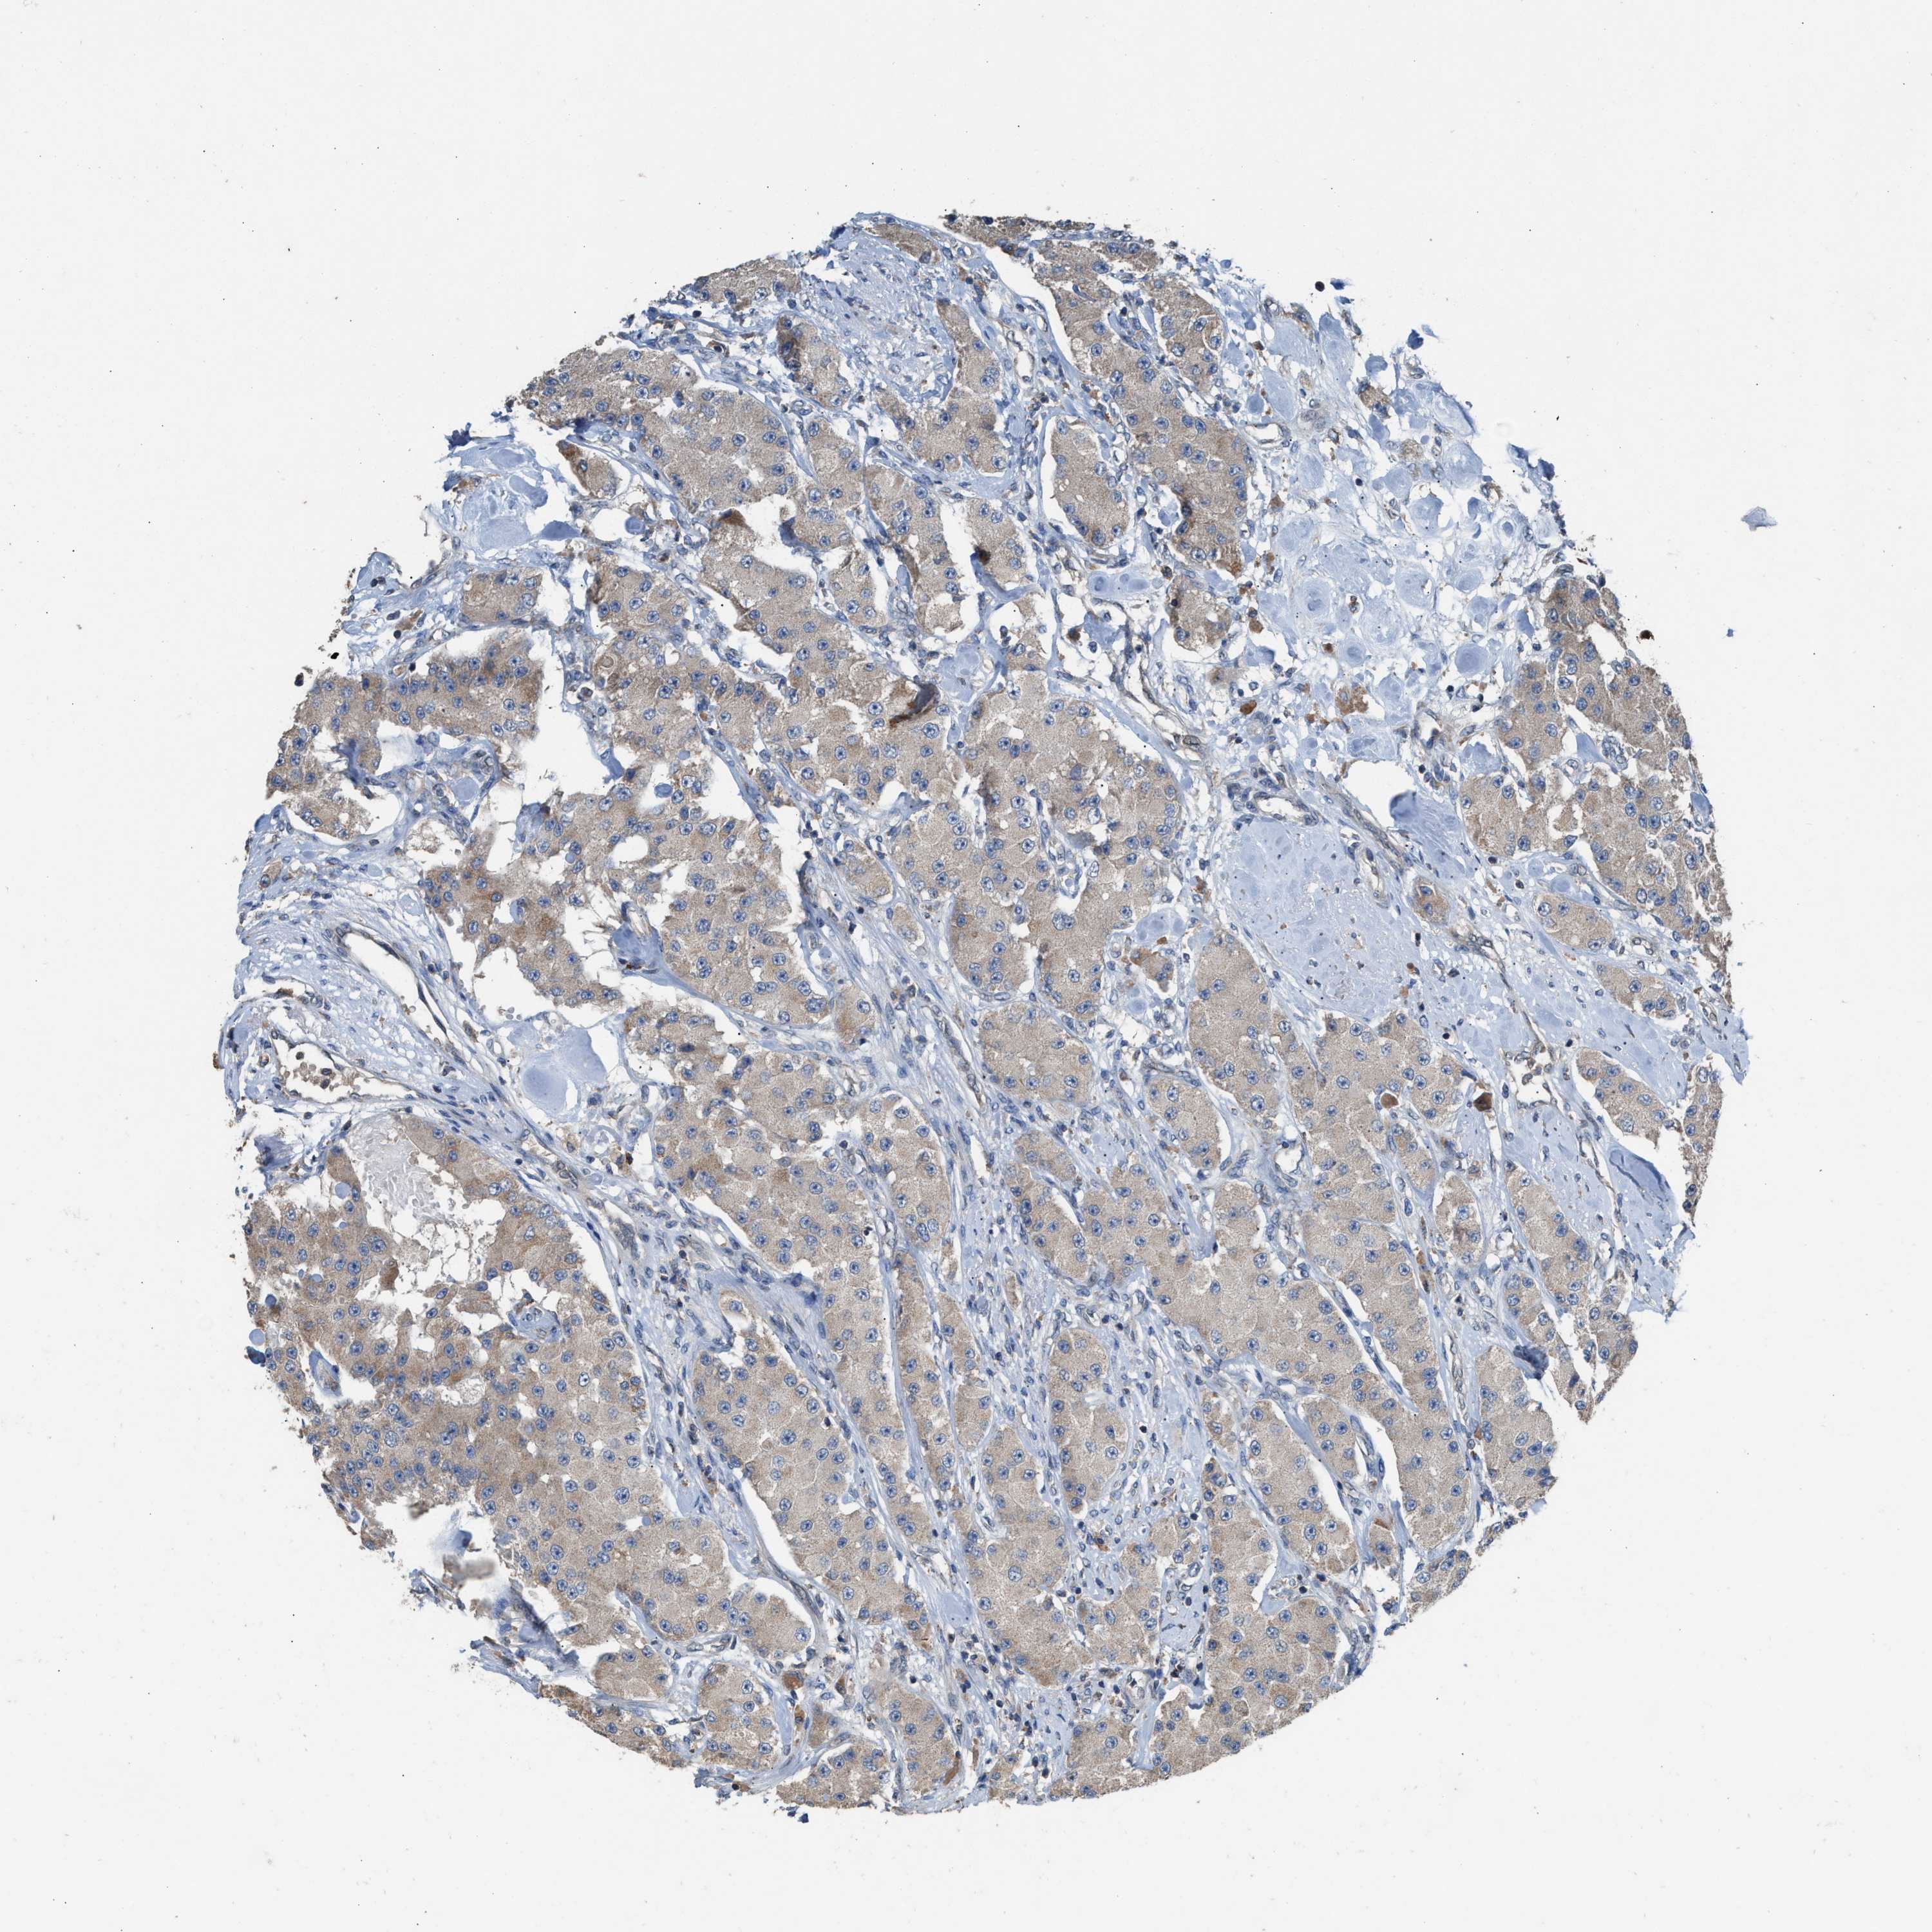

CARCINOID - Protein expressioni

A mouse-over function shows sample information and annotation data. Click on an image to view it in a full screen mode. Samples can be filtered based on level of antibody staining by selecting one or several of the following categories: high, medium, low and not detected. The assay and annotation is described here.

Antibody stainingi

Antibody staining in the annotated cell types in the current human tissue is reported as not detected, low, medium, or high, based on conventional immunohistochemistry profiling in selected tissues. This score is based on the combination of the staining intensity and fraction of stained cells.

Each image is clickable and will lead to virtual microscopy that enables deeper exploration of all samples and also displays staining intensity scores, fraction scores and subcellular localization as well as patient and tissue information for each sample.

Antibody HPA021545

Antibody HPA021849

Staining

High

Medium

Low

Not detected

Intensity

Strong

Moderate

Weak

Negative

Quantity

>75%

75%-25%

<25%

None

Location

Nuclear

Cytoplasmic/membranous

Cytoplasmic/membranous,nuclear

Carcinoid, malignant, NOS

Carcinoma, NOS